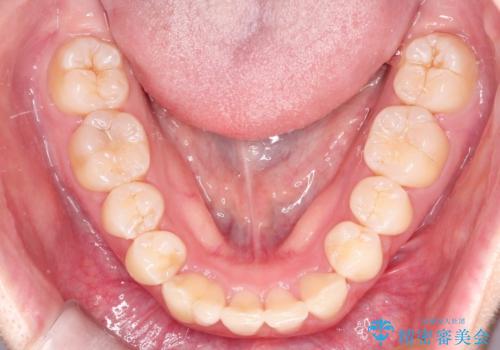

【インビザライン】抜歯矯正

- 前歯のガタガタを主訴に来院されました。

抜歯を行い、インビザラインにて治療を完了しております。